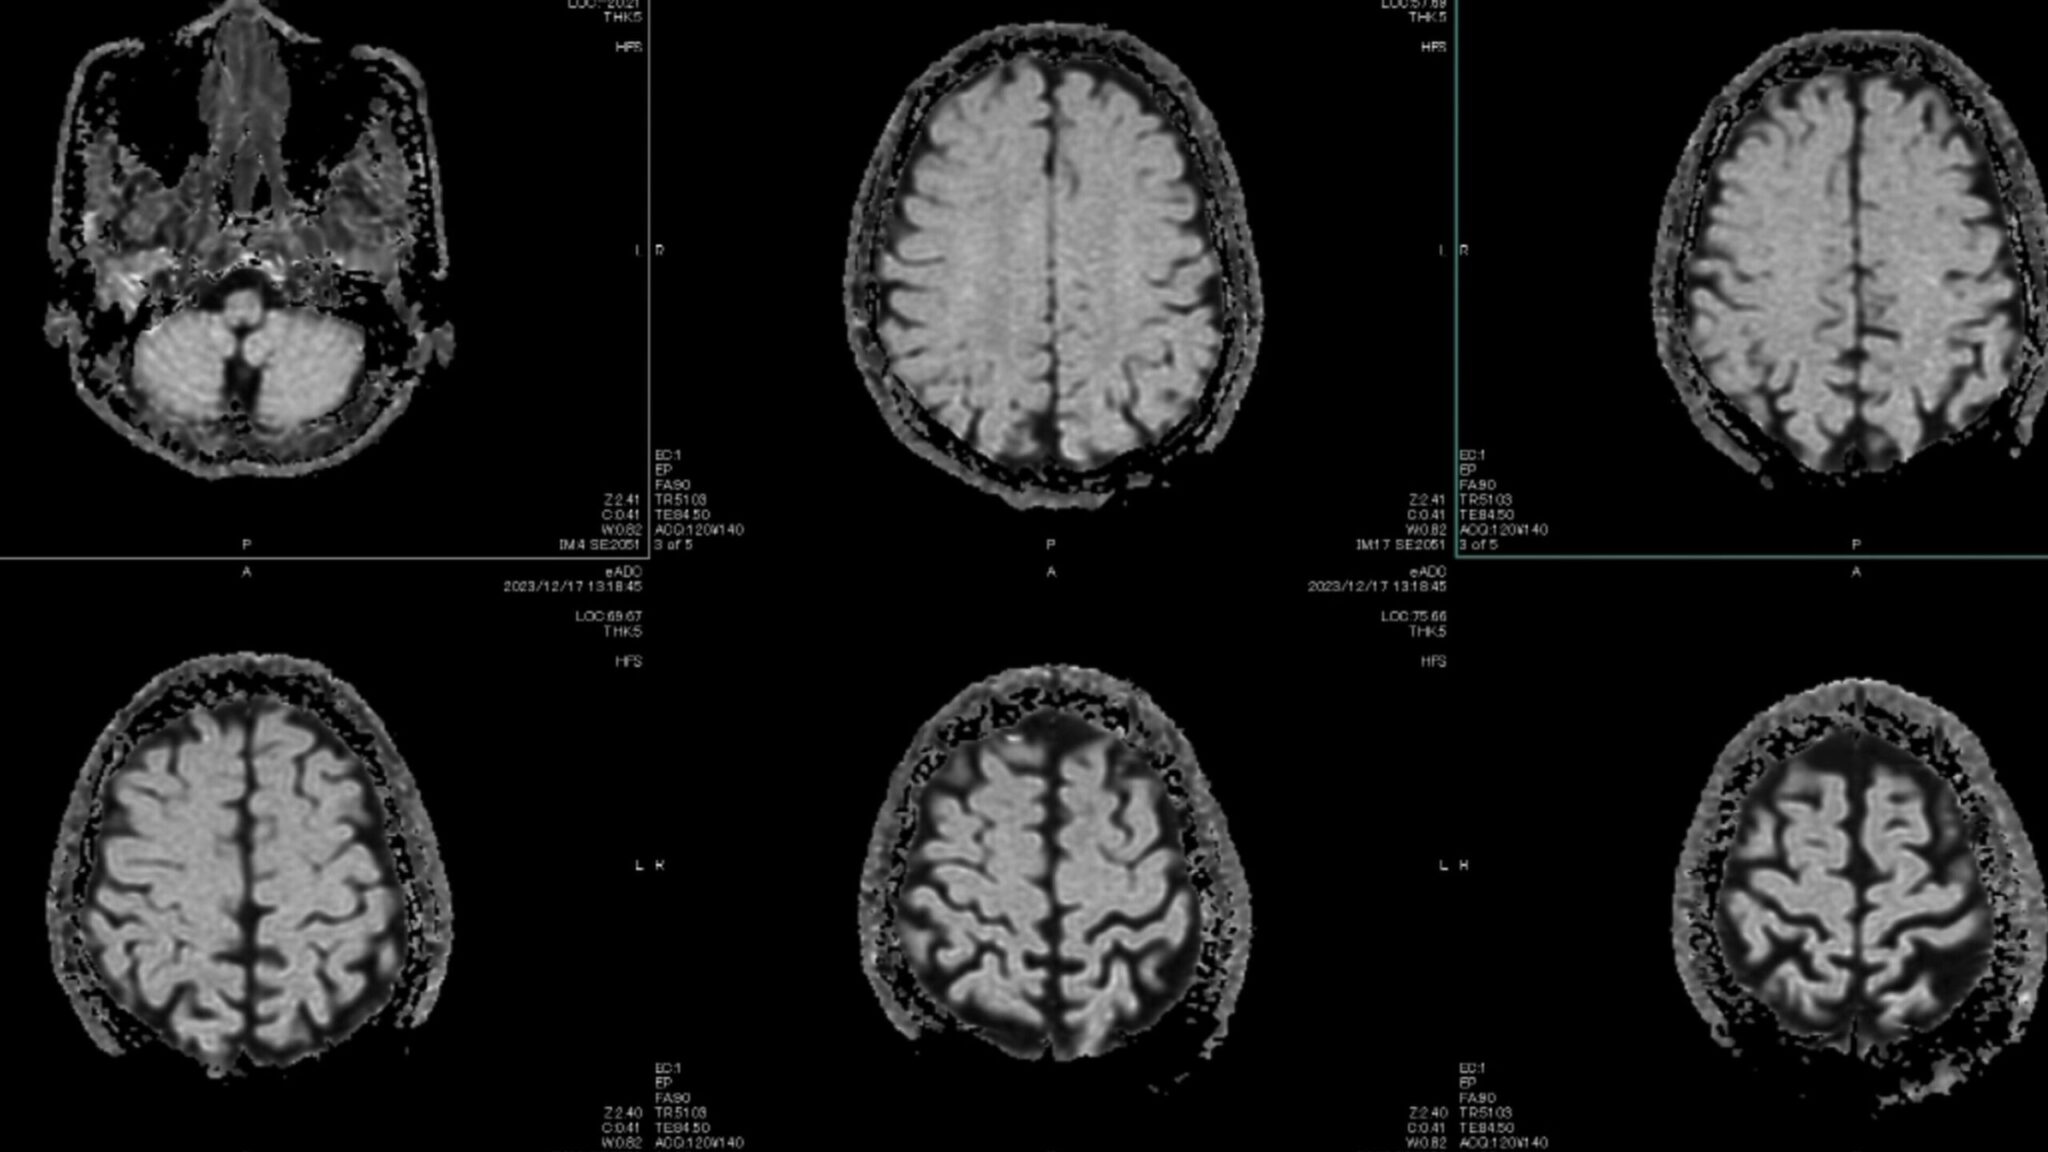

Καναδάς: Μυστηριώδης εγκεφαλική νόσος πλήττει νέους – Τι καταγγέλλει επιστήμονας